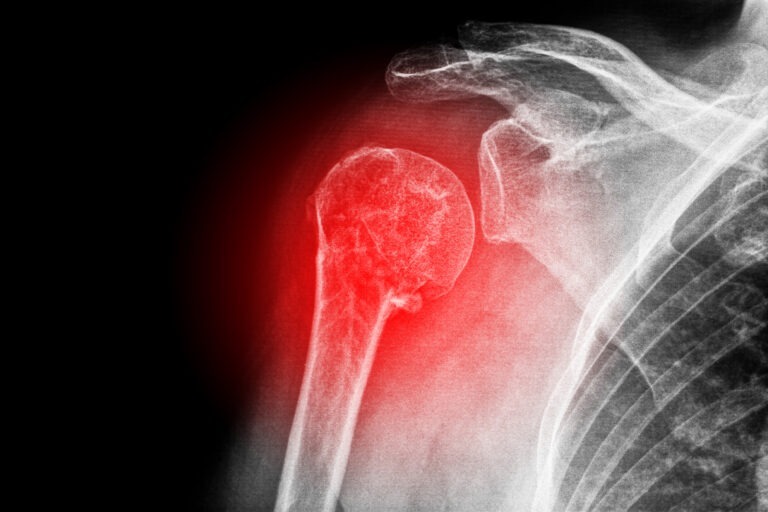

Frozen shoulder, also known as adhesive capsulitis, happens when the capsule surrounding your shoulder joint becomes thick and tight. As a result, scar tissue forms inside the joint, and the space where your arm bone sits becomes smaller. Consequently, your shoulder loses its normal range of motion and moving it causes significant pain.